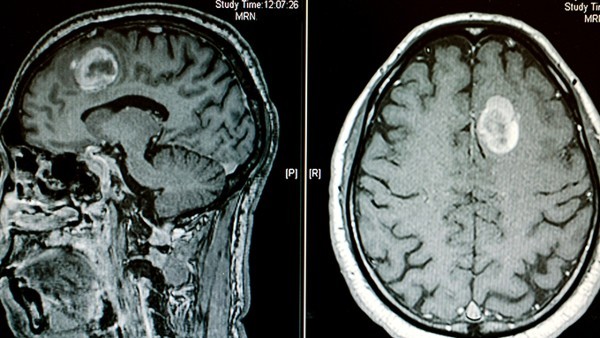

轻度脑梗塞的情况,其实是一种较为常见的病症,但是治疗难度也是比较大的,而且自身一生都是离不开药物的治疗的,所以,面对这类的情况,一定需要多加重视,并根据实际情况来进行处理,积极配合医生的治疗,所使用的药物种类也是比较多的,那么,轻度脑梗塞吃什么药好呢?